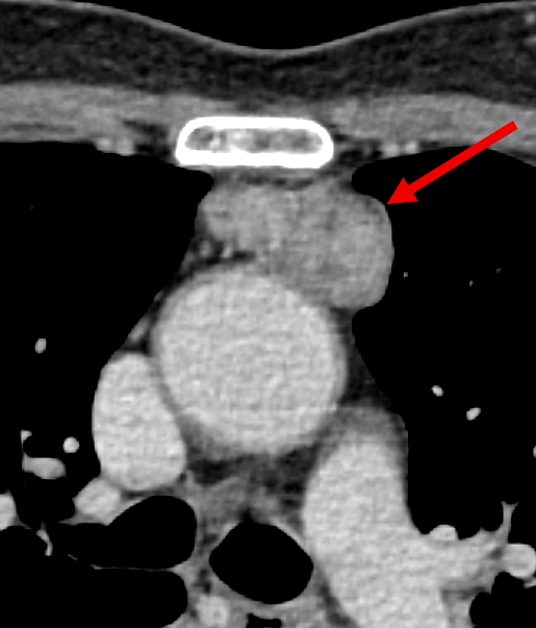

胸腺腫を疑う前縦隔腫瘍性病変の術前造影CT

健診の胸部単純X線写真にて異常陰影を指摘され、非造影CTにて胸腺腫が疑われた。手術目的で当院を受診し当該の造影CT検査を施行した。造影検査の結果、胸腺腫が完全に被包されており、周囲臓器への浸潤は認めず、リンパ節転移や遠隔転移を認めなかった。その後、撮像の約1か月後に胸腺腫疑い(cT1aN0M0 stageⅠ 正岡分類Ⅰ期)としてロボット支援下胸腺全摘術が施行された。病理診断ではWHO type A(低リスク群)であった。

今回の検査目的は縦隔腫瘤の術前精査であり、一般的な腫瘍性病変の精査と同様に大きさ、形態、性状、浸潤傾向の有無の確認という目的の他に、術式決定に必要な情報として動静脈の破格の有無や走行の確認、3Dシミュレーション用のVR画像作成がある。VR画像を作成することで立体構造が理解しやすくなるとともに、手術や気管支鏡等のナビゲーションに利用することができる。

この撮影は単純と動脈相と静脈相の撮影を行っている。静脈穿刺は左腕に行い、造影剤の注入は生理食塩水とのクロス注入を行っている。クロス注入を行うことによって鎖骨下静脈などの静脈路のCT値を低下させ、アーチファクトの低下を図ることができる。撮影はCannon社製のAquilion Precisionを使用し、スライス厚0.25mm、1024×1024マトリックスで画像作成をしており、高精細な撮影を行っている。これらによって細かい静脈である胸腺静脈の描出が認められやすくなる。造影剤投与量は17.3mg/kg/secとし、動脈相は40秒での後期動脈相の撮影、静脈相はA相から30secで撮影を行っている。撮影後の処理として、縦隔腫瘍と肺動静脈、大動脈、胸腺静脈を含めた上大静脈の位置関係の把握に有用なVR画像の作成を行っている。